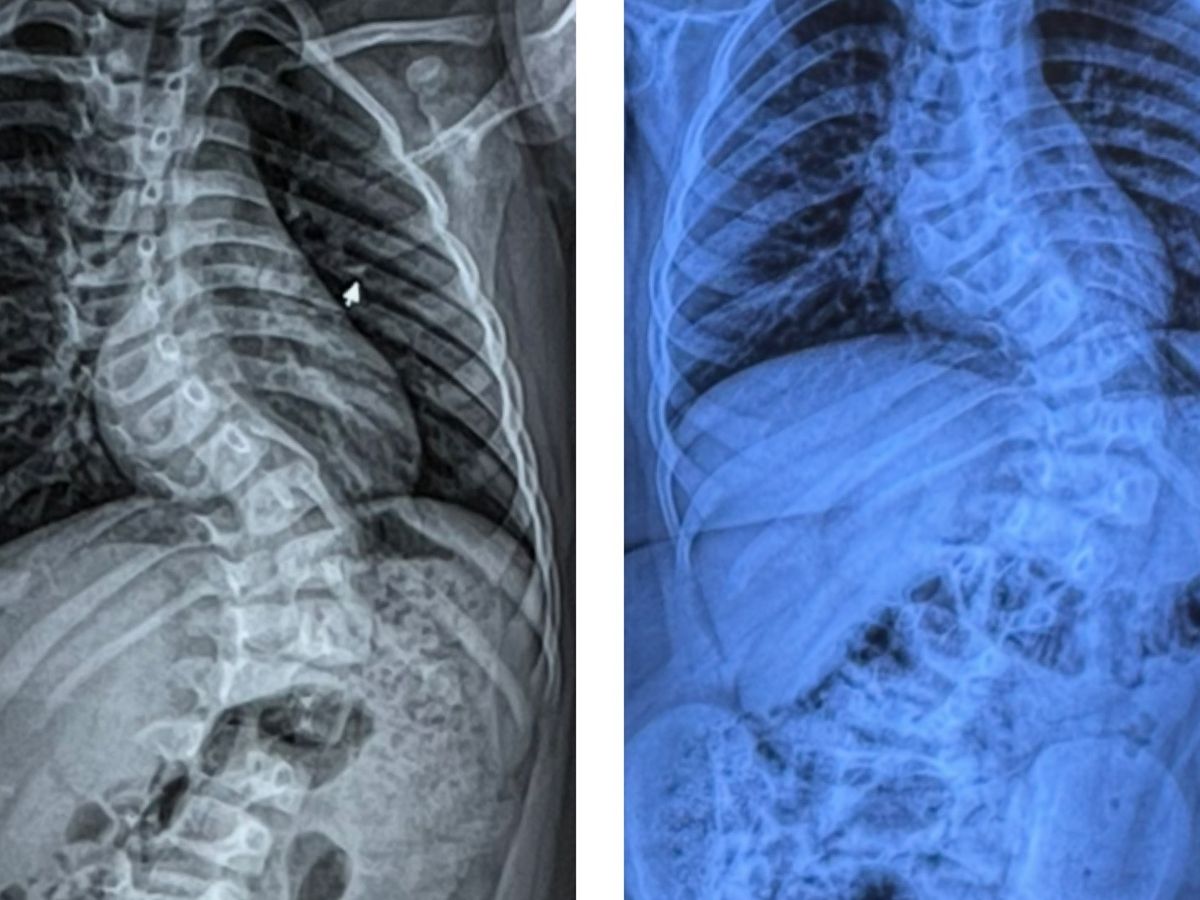

Koledyn was diagnosed with adolescent idiopathic scoliosis, double curvature, known as the (“S”) curved spine in November of 2022.

Scoliosis is a spinal deformity that causes an abnormal side-to-side curve in the spine..

Since, Koledyn has been seen at Essentia Health in Duluth, by Dr.Kathryn Huff and several other pediatric othoropedic specialists. Koledyns spine at this time had a 67 degree curve and a 43 degree curve.

Koledyn has had countless X-rays, an MRI to rule out cancer in his spine, and doctor visits every 3 months since the initial diagnosis in 2022.